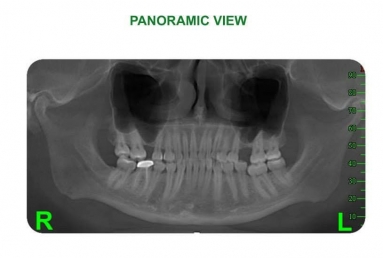

Orthodontic treatment, external sinus lifting.

Orthodontic treatment, external sinus lifting, dental implant and zirconium crown.